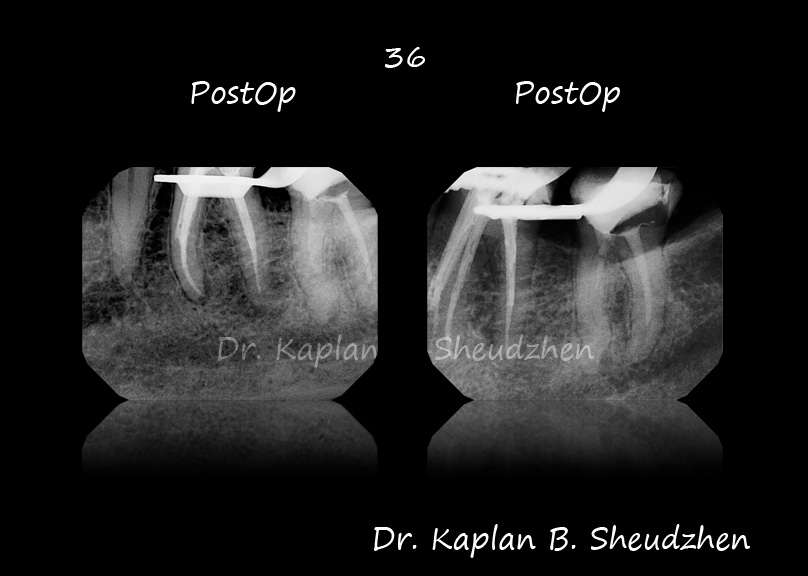

36. плановый ретрит. снимок до - с панорамника. коффердам, доступ, в каналах паста+грязь+дентикл. беру набор мту и глядя на него мысль - надо будет после этой эндодонтии выкинуть весь наборчик и поставить новые файлы. Д - пройден без проблем, МЯ-пройден без проблем МБ - прошел до упора пилотом и 15.02. ну думаю, раз упирается, хоть постараюсь типа краун-даун сделать. 10.04-15.05 до упора, и грохнул мту 20.06 на упоре. помыл, кальций, отпустил. во второй визит все же достал отломок, но дальше упора не прошел. сегодня еще постарался пройти, но безуспешно. дальше упора никак. запаковал. заступенил прилично. в оптику видел и ступень и ход. но ни один файл не пошел дальше упора.